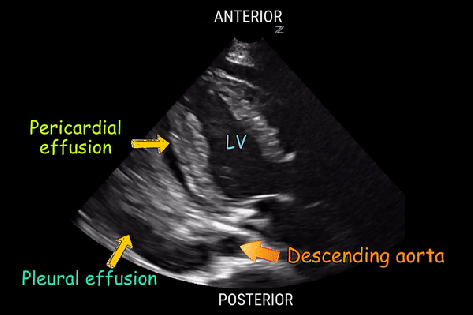

- Pericardial vs pleural effusion on POCUS peristernal long axis (PLAX)

- Pericardial: fluid ANTERIOR to the descending aorta

- Pleural: fluid POSTERIOR to the descending aorta